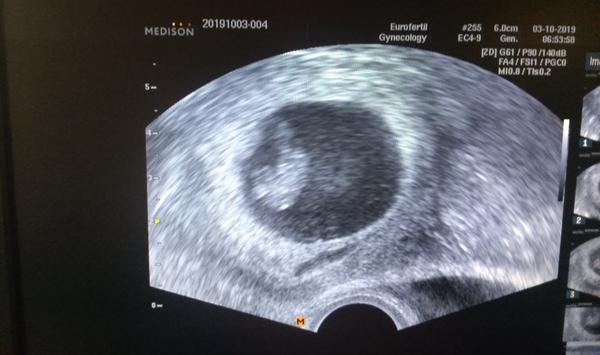

@barcachejn ahoj. Jsem 13+4 a dnes mi dělali prvotrimestrální screening. Všechno v pořádku a miminku se daří. Držím palce a nenervuj se 🙂